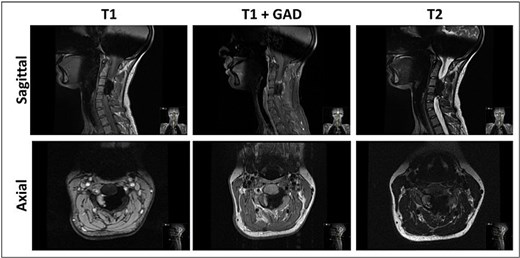

Magnetic resonance imaging (MRI) of the cervical spine demonstrated a hyperostotic lesion extending from C2 to C5. The lesion appeared predominantly intraosseous with periosteal extension but without involvement of adjacent soft tissues. There was significant left-sided spinal canal encroachment, resulting in severe cord compression (canal narrowing <5 mm). T2-weighted sequences showed deformation and signal changes within the spinal cord consistent with compressive myelopathy (Fig. 1). Complementary computed tomography (CT) revealed dense cortical hyperostosis with a characteristic “dripping candle wax” appearance (Fig. 2).

MRI sagittal and axial views of the cervical spine demonstrating non-enhancing, hypointense in all sequences, calcified lesion involving mainly C3–C4, causing severe compression of the spinal cord with hyperintense signal, indicating myelomalacia.